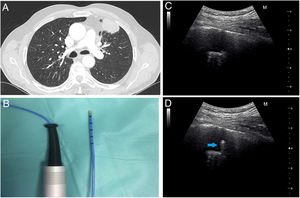

The first patient was a 76-year-old male, a heavy ex-smoker with a peripheral left mass on chest X-ray. Thoracic computed tomography (CT) revealed a lingular solid mass with 38mm larger diameter, based on pleura adjacent to the anterior thoracic wall (Fig. 1A) compatible with primary lung neoplasia. Chest ultrasound examination showed a nodule of 26mm of maximum depth with pleural contact, mobile with respiratory movements and partially covered by the adjacent rib, leaving a narrow intercostal space for examination. Standard bronchoscopy with a thin bronchoscope, showed no endobronchial lesions so the endoscopic examination was carried out with r-EBUS. A 1.4mm radial ultrasound probe (Olympus Co, Japan) was advanced through the lingula bronchi until the hypoechoic heterogeneous nodule was visualized and then we tried to reproduce the path with the 1.9mm cryoprobe (ERBE CA, Germany) (Fig. 1B). Prior to transbronchial sampling, the transthoracic ultrasound (convex transducer, F2.5MHz D9.9, MINDRAY Co, China) was applied on the anterior chest wall (Fig. 1C) and was able to visualize, in real time, the transbronchial cryoprobe going through the mass and avoiding the pleura (Fig. 1D and supplementary video 1A). Curiously, applying freezing decreased the ultrasound image of the probe, except for the tip (supplementary video 1B), and allowed for the visualization of the tissue freezing process. Biopsies (4 samples, 1.1×0.9×0.3cm) were positive for adenocarcinoma.

(A) Chest CT image shows a lingular mass with pleural contact and bronchus sign. (B) Flexible cryoprobe indicated for transbronchial biopsy. Outer diameter 1.9mm, length 900mm. (C) Transthoracic ultrasound image before performing transbronchial biopsy of the mass. (D) Transthoracic ultrasound image during the performance of transbronchial biopsy, which locates the cryoprobe within the lung mass (arrow).